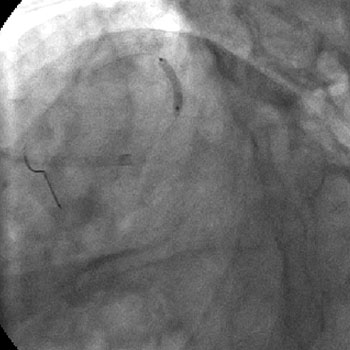

3) LAD: Ostial CTO ( Figure 2) with collaterals from RCA and LCX (Figure 3).